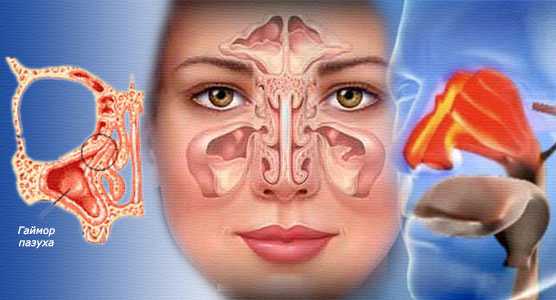

В большинстве случаев, чтобы полностью избавить больного от кисты в пазухе носа, требуется малое хирургическое вмешательство. Это становится понятным, если увидеть, как выглядит такое образование.

Кистозный узел – это полый пузырь с жидким содержимым, слизью или гноем в полости носа, который не способен исчезнуть под влиянием лекарств или домашних средств народной терапии.

В каких условиях допустимо консервативное лечение

Чтобы понять, почему можно лечиться без хирургического вмешательства, нужно разобраться, чем же является сама киста. Это доброкачественное новообразование, внешне оно напоминает шарик, наполненный жидкостью. Выбирать консервативные методы лечения можно потому, что киста не дает метастазы и не затрагивает другие органы, она полностью безопасна для организма, если имеет небольшой размер и не воспалена.

Причины

В придаточных носовых пазухах на слизистой оболочке располагаются особые железы, которые вырабатывают слизь, требующуюся для увлажнения полости носа. У каждой железы есть отдельные протоки для вывода своего секрета на поверхность слизистой. Если эти протоки полностью или частично забиваются, то в придаточных пазухах носа может скапливаться слизь. Поскольку железа так и продолжает работу, а выходить слизи некуда, стенки железы под давлением расширяются – так и образуется киста.

Что такое киста

Киста в пазухе – это мешкообразное доброкачественное новообразование круглой формы с жидким содержимым. Оно формируется в результате длительного воспалительного процесса – организм защищается от инфекции, поэтому и ограждает ее очаг капсулой.